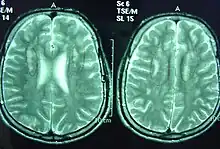

Sjögren–Larsson syndrome is a rare autosomal recessive form of ichthyosis with neurological symptoms.[1]: 485 [2]: 564 [3] It can be identified by a triad of medical disorders. The first is ichthyosis, which is a buildup of skin to form a scale-like covering that causes dry skin and other problems. The second identifier is paraplegia which is characterized by leg spasms. The final identifier is intellectual delay.

SLS is caused by a mutation in the fatty aldehyde dehydrogenase gene found on chromosome 17.[4] In order for a child to receive SLS both parents must be carriers of the SLS gene. If they are carriers their child has a 1/4 chance of getting the disease. In 1957 Sjögren and Larsson proposed that the Swedes with the disease all descended from a common ancestor 600 years ago. Today only 30–40 persons in Sweden have this disease.[5]